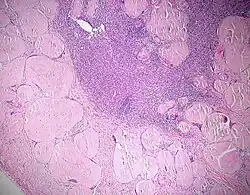

- Käsige Nekrose - Bsp.: Tbc (Epitheloidzelliges Granulom mit Langhans-Riesenzellen und zentraler käsiger Nekrose)

- Spezifische Entzündung - Entzündungsmanifestationen, die für eine Erkrankung typisch sind z.B. Tbc, Sarkoidose